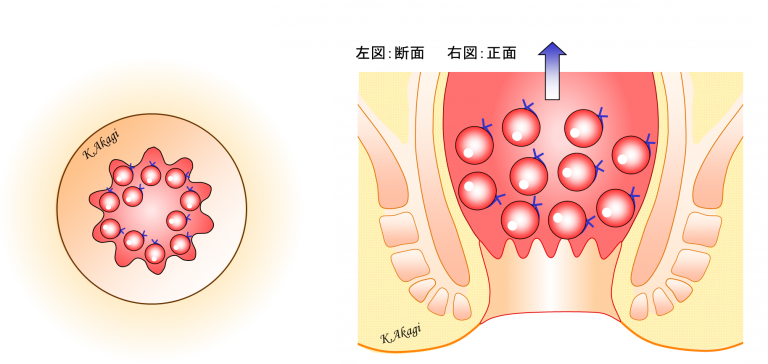

直腸瘤 よくわかる大腸肛門科

骨盤臓器脱 亀田メディカルセンター ウロギネ 女性排尿機能センター

排便障害 よくわかる大腸肛門科